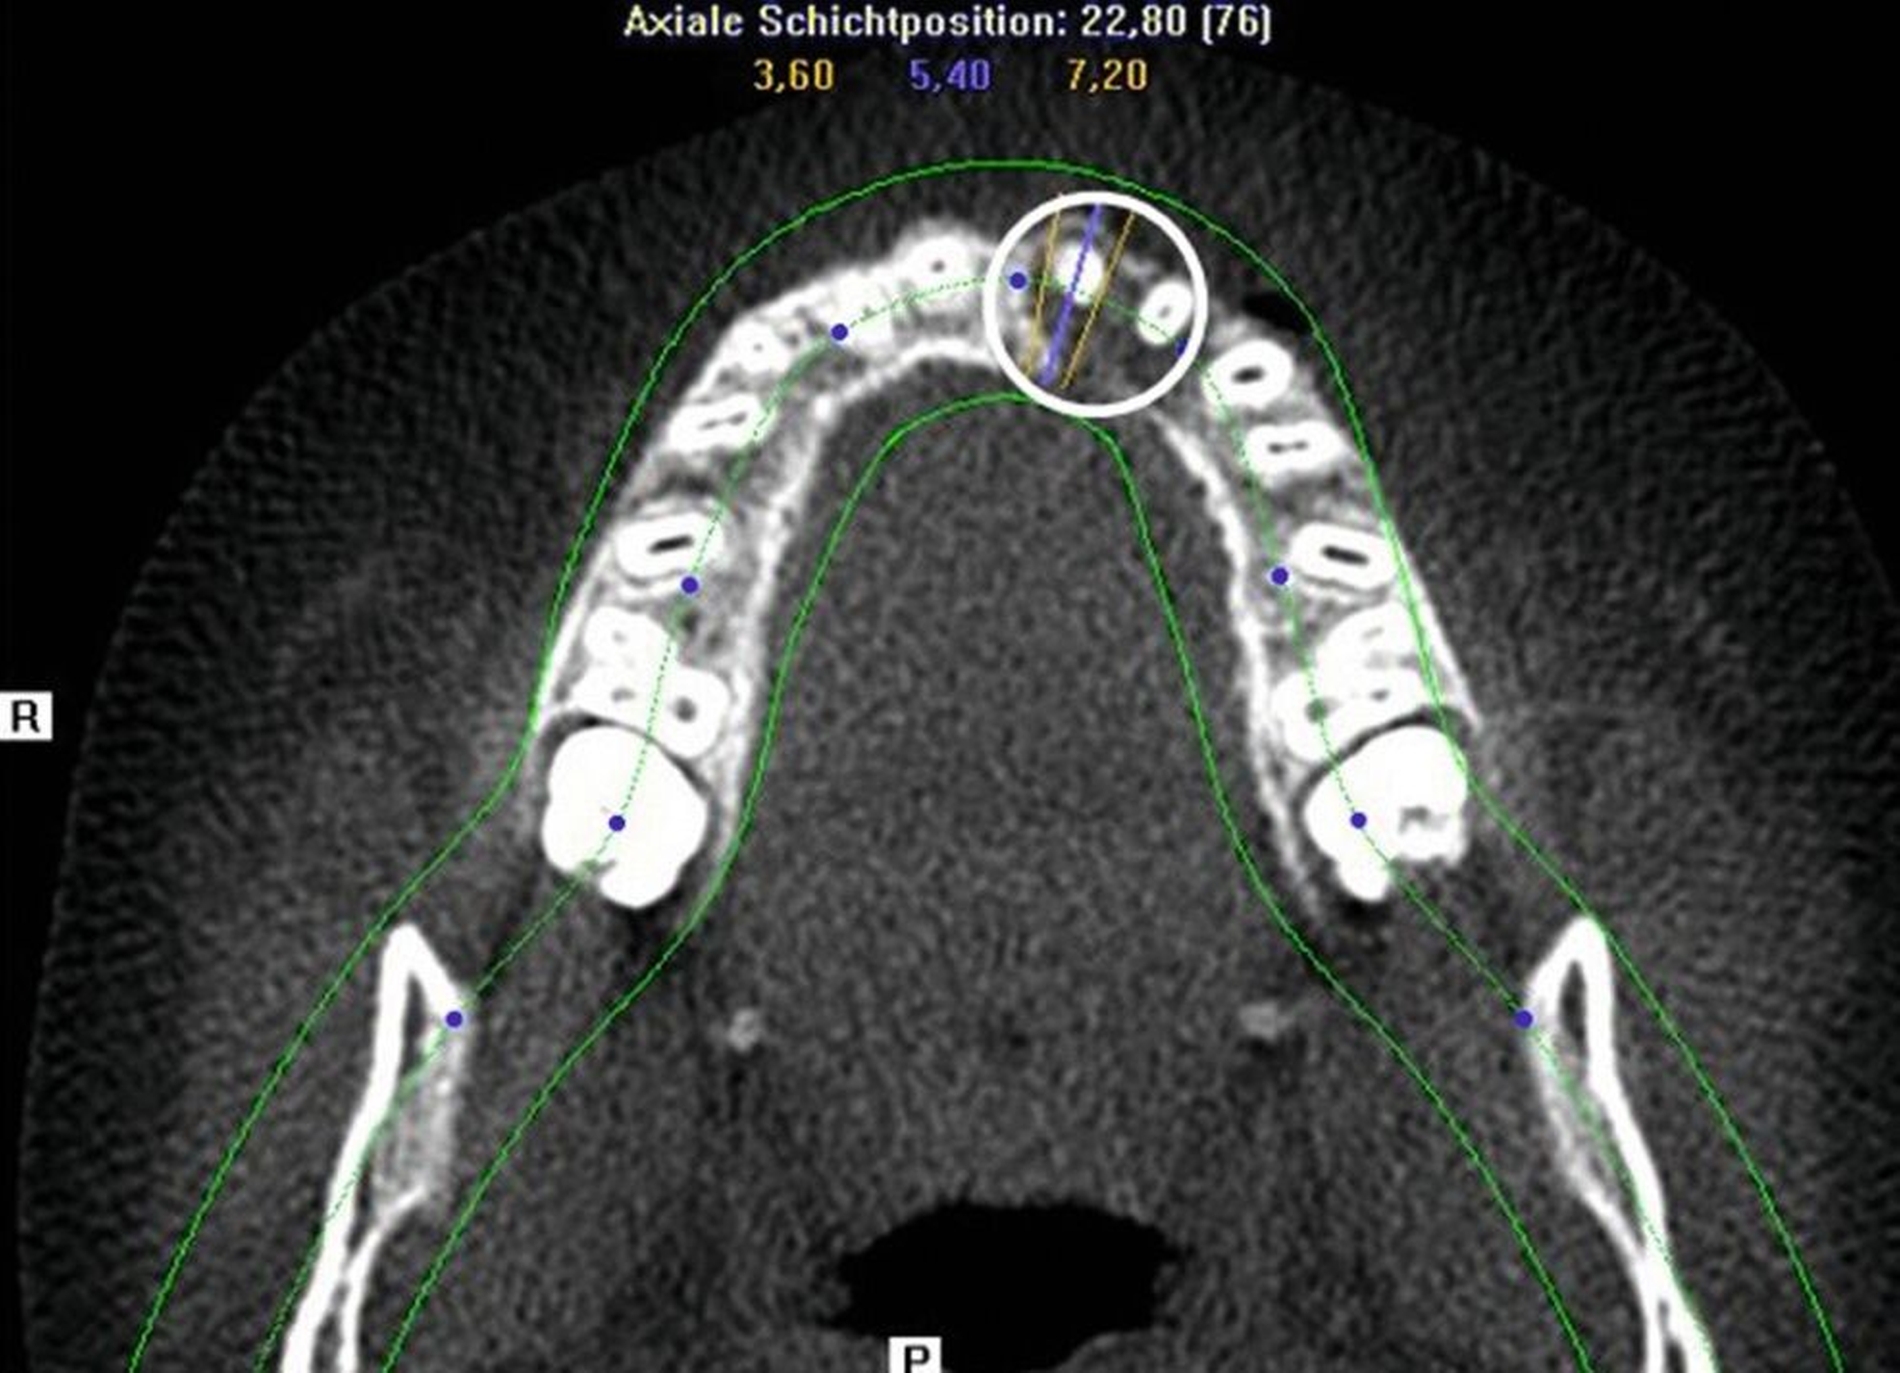

Zur weiteren Abklärung wurde eine dreidimensionale Aufnahme durchgeführt (DVT). Dabei bestätigte sich die erhebliche Osteolysezone im apikalen Bereich des vormals traumatisierten Zahnes 21. Der Zahn 13 stellt sich hoch verlagert am Nasenboden dar, während es bei dem persistierenden Milchzahn 53 zu einem natürlichen Lückenschluss in regio 13 gekommen ist (Abbildung 2).

Auf Empfehlung des mitbehandelnden Kieferorthopäden sollte der natürliche Lückenschluss in regio 53 belassen und die autogene Transplantation des verlagerten Eckzahns 13 an die Stelle des verloren gegangenen Zahnes 21 durchgeführt werden. Der Eckzahn 13 wurde etwa einen Monat später in die Region 21 transplantiert und am zuvor eingebrachten kieferorthopädischen Bogen kunststoffadhäsiv fixiert (Abbildung 4).